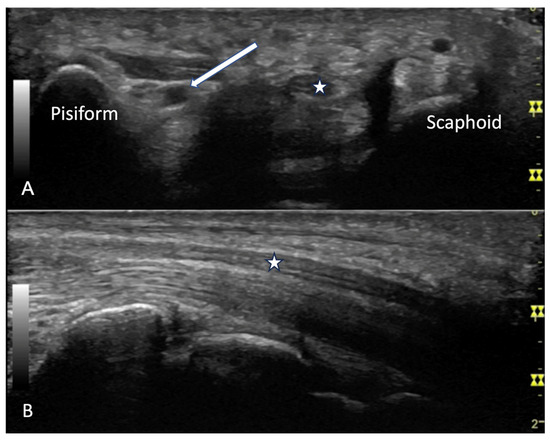

2.2.2. Contractures and Tendon Friction Rubs

4.2.2. Volar Aspect

4.2.3. Ulnar Aspect